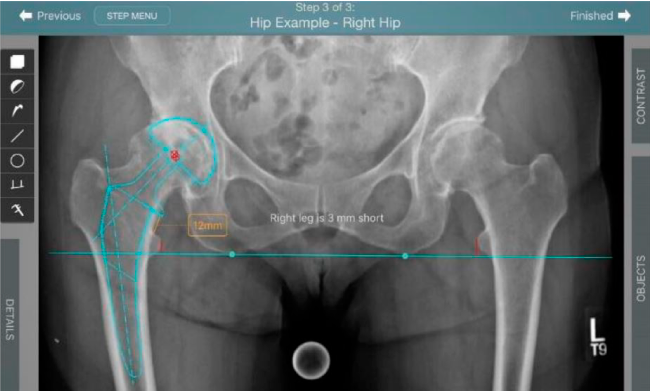

Planeación preoperatoria mediante la creación de plantillas digitales para reemplazo de cadera y análisis intraoperatorio

Anotaciones digitales y herramientas de análisis de longitud de pierna.

Con tecnología ONETRIAL® que calcula automáticamente el cambio en la longitud de la pierna y el desplazamiento para todas las combinaciones de implantes en una tabla fácil de leer.